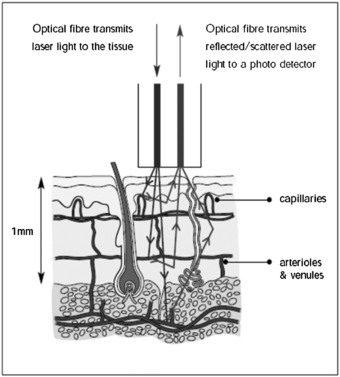

Laser Doppler flowmetry (LDF) uses the frequency shift of low-power (typically in the region of 1 to 5 mW and single mode) laser light produced by the Doppler effect to assess tissue blood flow (Oberg et al 1979). The initial development was single point measurement technology using fibre-optics, with developments in imaging coming to fruition in the early 1990s (Essex and Byrne 1991, Wårdell et al 1993). Depending on the laser wavelength employed, LDF can assess blood flow in the nutritional capillaries close to the skin surface and the underlying arterioles and venules deeper in the dermis involved in regulation of skin temperature (figure 1). LDF could also be used for other tissues when exposed at surgery, e.g. colonic blood flow (Hajivassiliou et al 1998). The tissue thickness sampled by a red or infrared laser system is typically 1 mm, the capillary diameters 10 µm and the erythrocyte velocity range 0.01 to 10 mm s−1. Blood flow information can also be available for the larger elements of the microvasculature, i.e. 100 µm, although LDF underestimates flow when these vessels are vasodilated due to system bandwidth limitations.

Figure 1. Dermal layers and microcirculation probed by laser Doppler techniques. (Courtesy of Moor Instruments.)